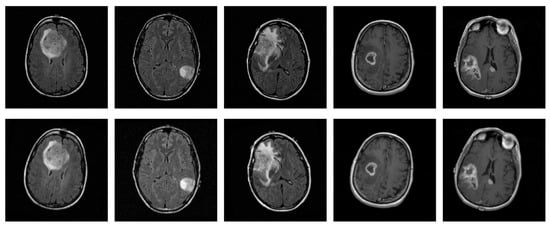

2.1. Data Collection